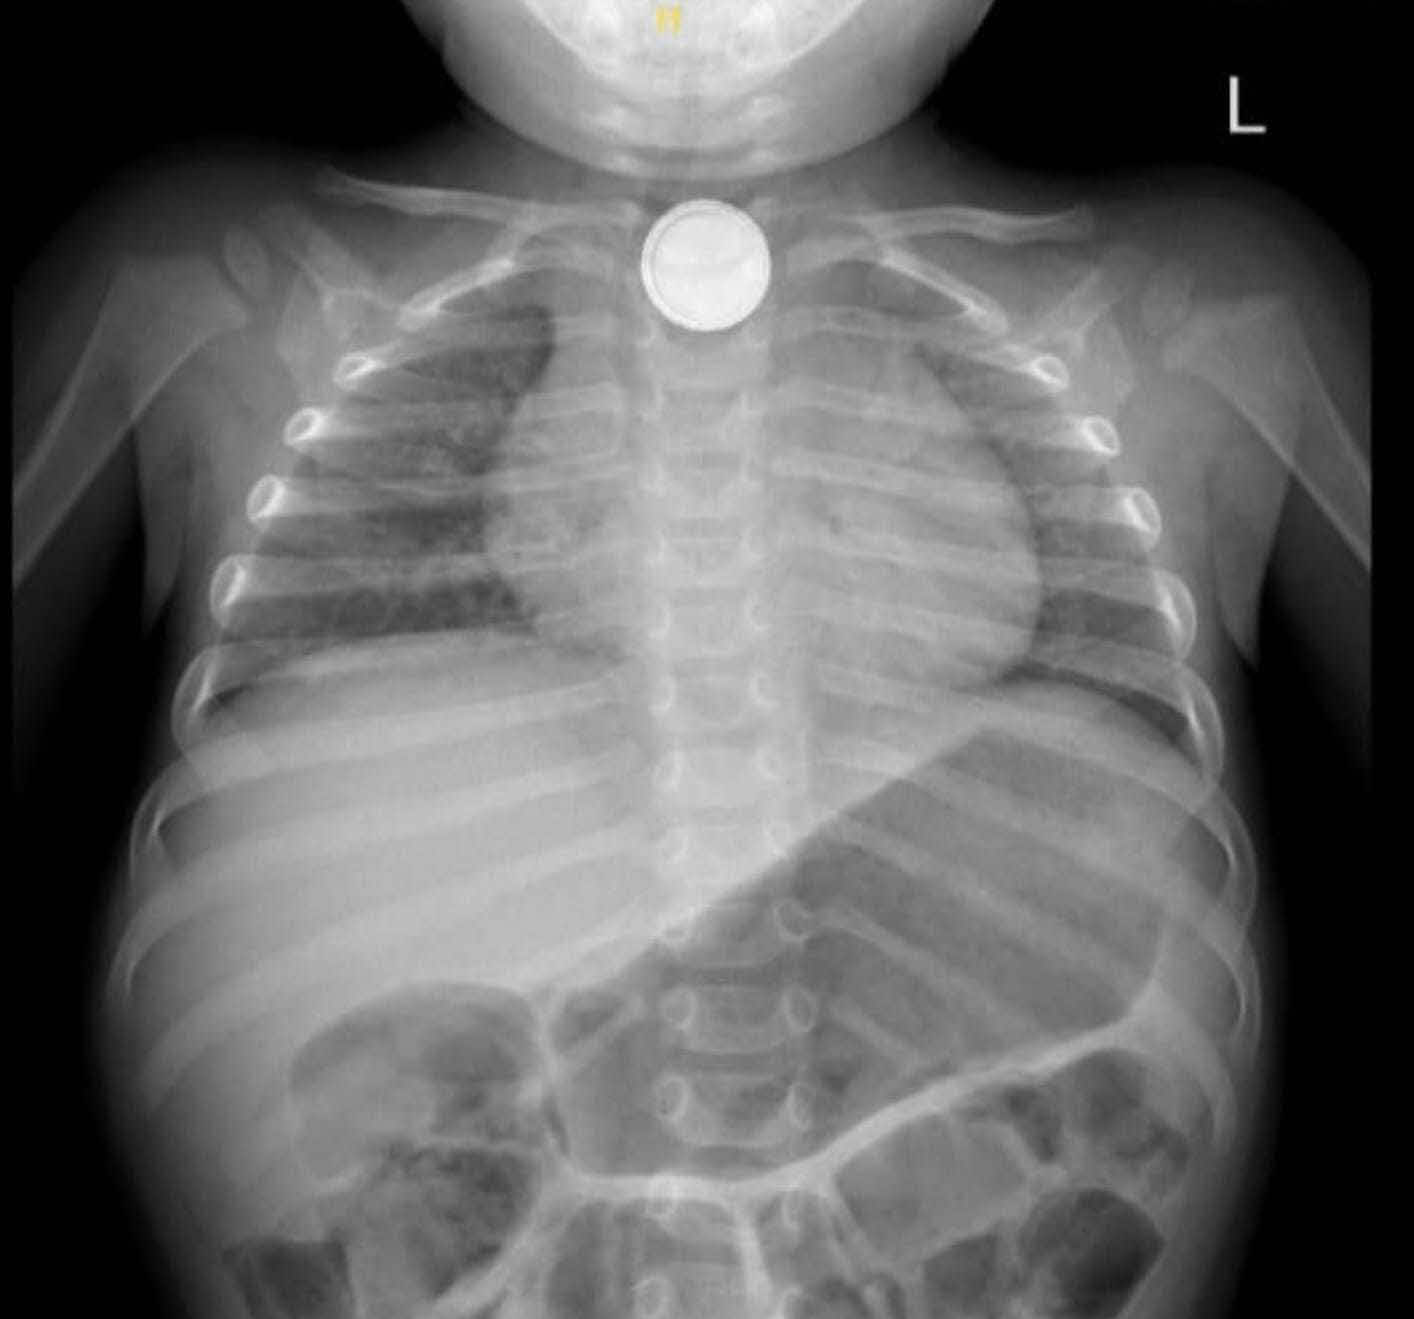

עם הגעתו למיון, משה סבל מקושי בבליעה וריור והוגדר במצב של סכנת חיים. ד"ר דניאל כהנא, מתמחה ברפואת ילדים, קיבלה אותו במלר"ד הילדים וזיהתה במהירות את חומרת המצב. בצילום רנטגן אובחנה הסוללה בוושט העליון.